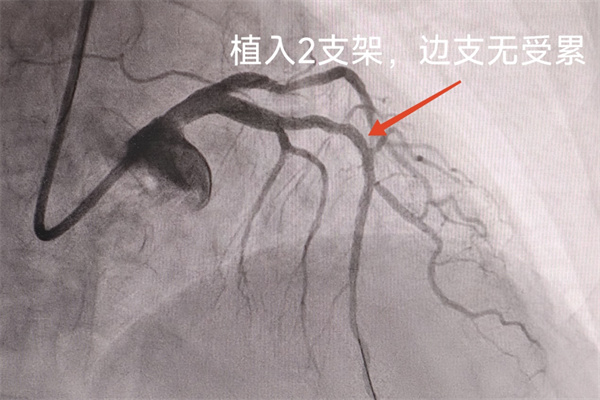

尽管已有心理准备,但看到王奶奶的造影图像,在场众人仍不禁倒抽一口冷气:前降支中段几乎完全闭塞,还可见附壁血栓,前向血流严重受限!

王奶奶高龄、体重低,且冠脉病变严重,这些都是影响其围术期安全的重大不利因素。“老人家放心,我们很有信心!”冯世兴医生为王奶奶加油打气。老年心血管中心主任王健主任医师带领的冠脉介入团队医术高超、经验丰富,是应对高难度手术的坚实保障。在与王健主任医师、贾丁主治医师的默契配合以及介入团队的全力协作下,仅用时15分钟,冯医生便成功为王奶奶的心脏血管植入2枚药物支架,术后血流恢复通畅。